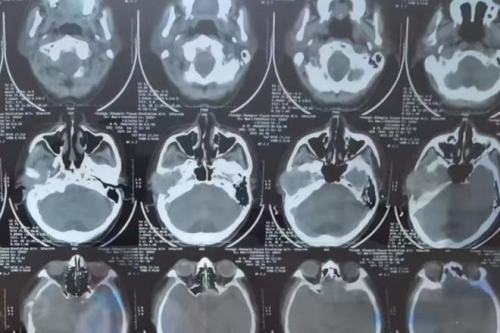

接诊张大爷的是郑州民生耳鼻喉医院特聘专家娄卫华教授,他是一位国内知名的耳鼻喉科专家。在详细了解病史后,娄教授安排了多项检查,包括CT影像和耳内窥镜分析。结果显示,张大爷的右侧颞骨处存在一个明显肿物。结合临床症状与影像学表现,娄教授判断为“右侧颞骨肿瘤”,建议尽快手术切除,并通过病理分析进一步明确性质。

颞骨区域结构复杂,紧邻多个重要神经及血管,手术操作难度较高。如果稍有不慎,可能导致面瘫或听力永久丧失等严重后果。面对风险,娄卫华教授组织团队进行了周密的术前讨论,根据患者年龄、身体状况及病情特点,制定了一套精准且微创的手术方案,既能完整切除肿物,又最大限度保护周围正常组织。

手术当天,由娄卫华教授亲自操刀,凭借丰富的临床经验及精湛技术,顺利完成了“右侧颞骨肿瘤切除术”。术中操作精准,出血量少,患者情况稳定。术后病理结果显示肿物为良性,彻底排除了恶性肿瘤的可能,这让张大爷一家人悬着的心终于放了下来。